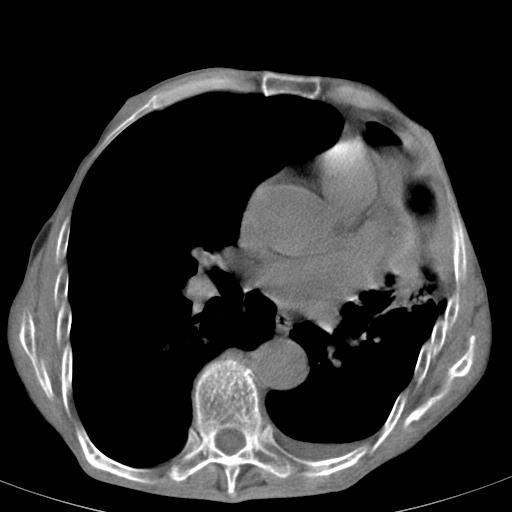

患者78岁,咳嗽胸闷一年余,近月来左侧胸痛;

左侧少量胸腔积液,局限胸膜增厚,结合病史,考虑慢性肺炎.

患者左侧胸廓塌陷说明是长期病变,考虑tb性胸膜炎可能性大,另外有明显的肺气肿,建议行结核菌素实验,或者增强扫描

1.慢支肺气肿。2.左肺感染,建议治疗后复查。3.左侧少量胸水。

1.慢支肺气肿。2.左肺感染,建议治疗后复查,待除外继发性肺结核合并感染。3.左侧少量胸水。

1)考虑左肺慢性感染性病变(结核可能)。2)左肺上叶周围型肺癌不排除;建议追踪复查。3)肺气肿。4)左侧胸腔积液,左侧胸膜增厚、粘连。